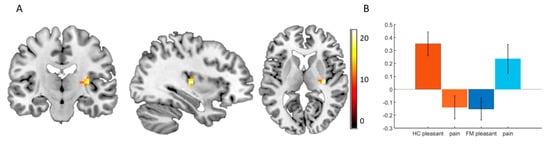

3.3. Functional Imaging

4.2. Functional Imaging